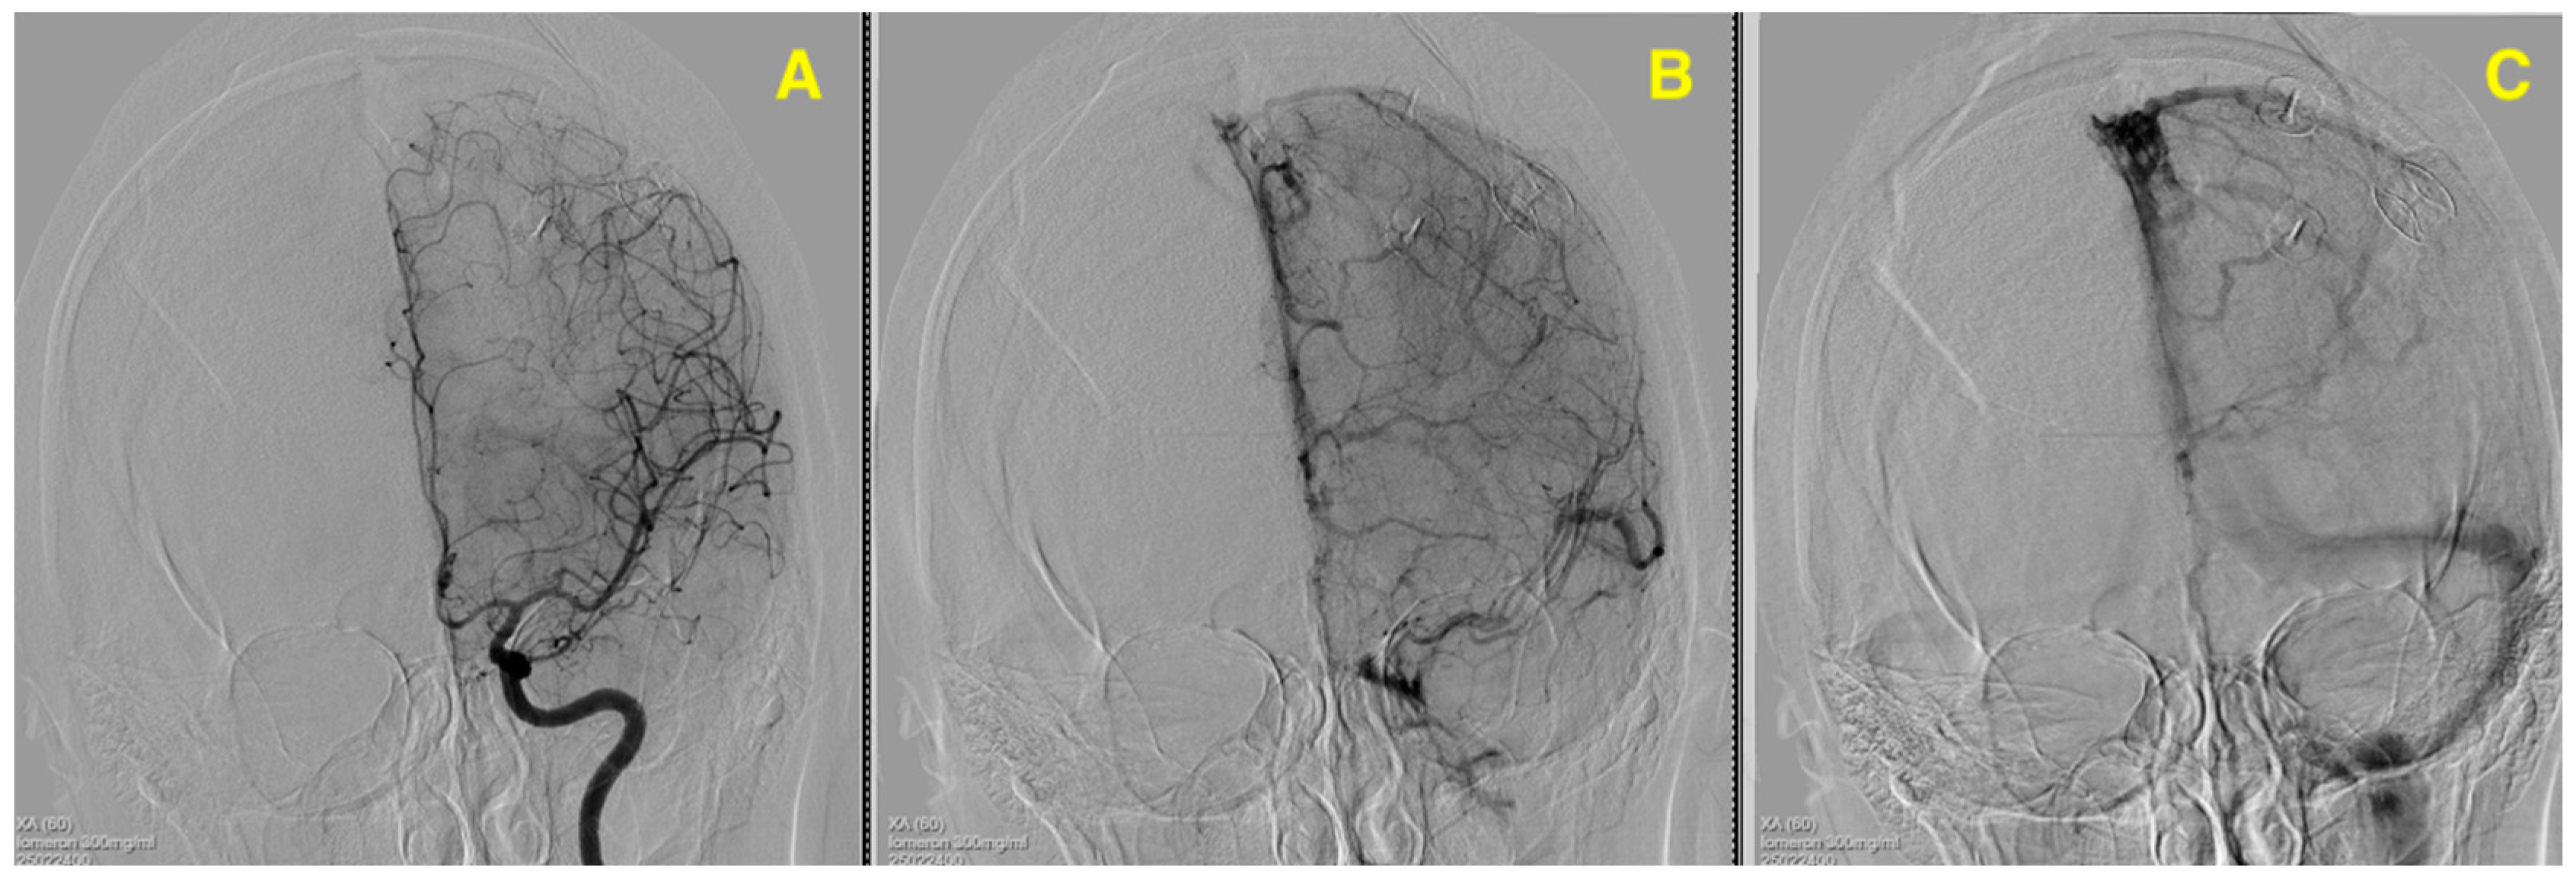

Challenging Management of a Rare Complex Cerebral Arteriovenous Malformation in the Corpus Callosum and Post-Central Gyrus: A Case Study of a 41-Year-Old Female

2. Case Presentation